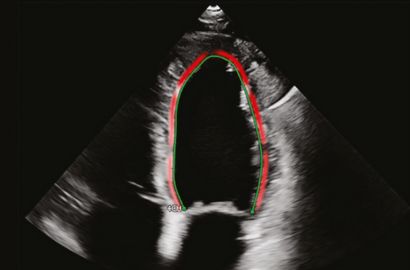

Strain Echocardiography (GLS): Advanced Insights into Heart Function

Strain echocardiography, also known as Global Longitudinal Strain (GLS), is an advanced imaging technique that goes beyond traditional 2D echo. It evaluates the subtle movements of the heart muscle to detect early signs of dysfunction, even before symptoms appear.

• Advanced technology: Performed using a dedictaed Philips echocardiography machine with strain imaging powered by the industry leader TOMTEC software for precise analysis.